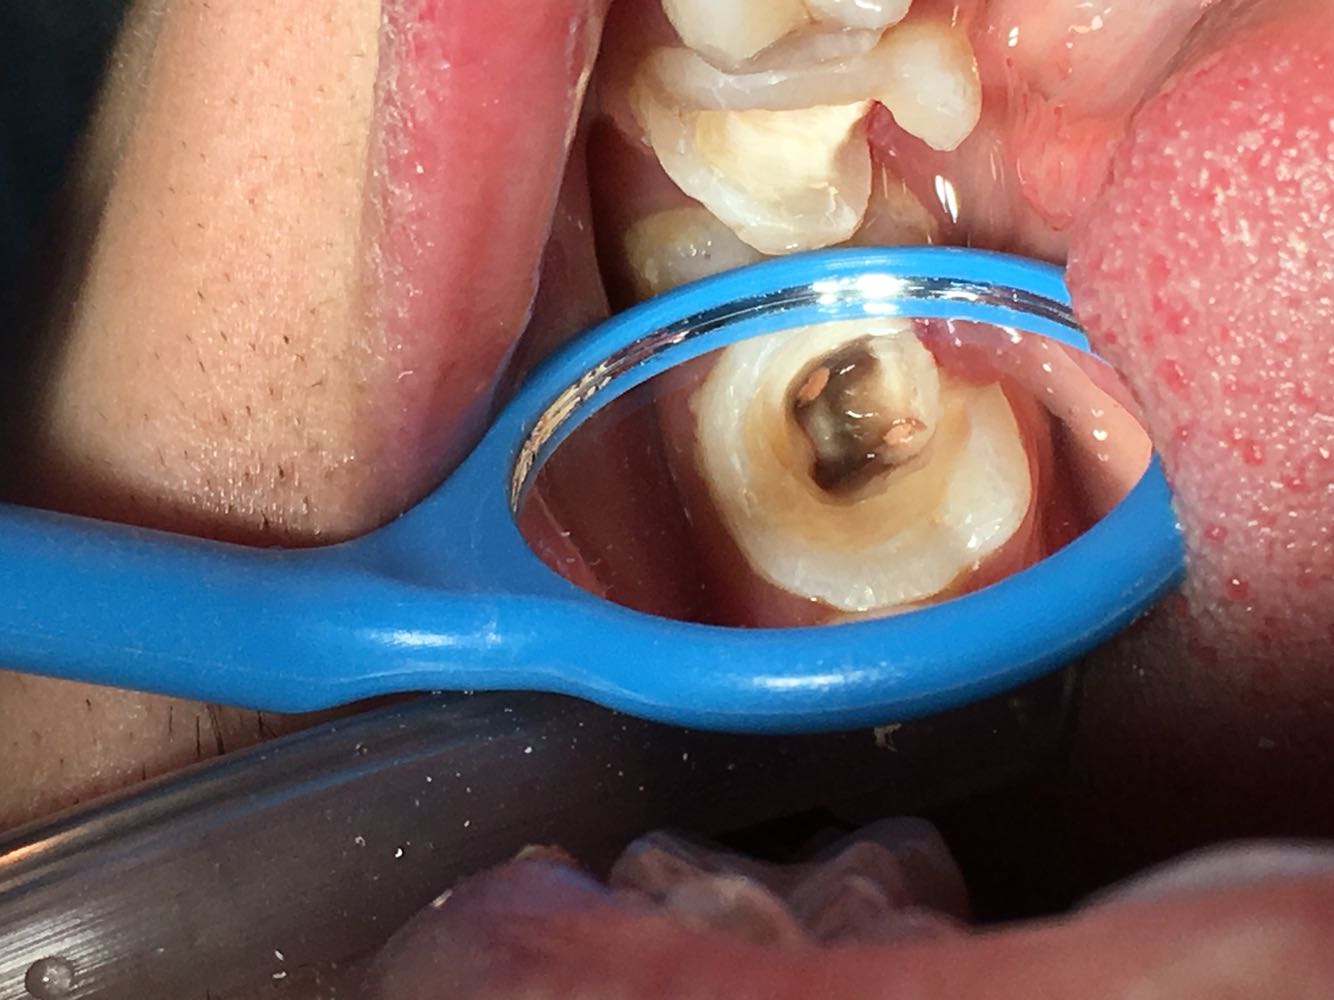

主诉:左下后牙牙冠部分劈裂1天 现病史: 1天前咬硬物时左下后牙牙冠部分劈裂,现就诊我科要求冠修复治疗,否认自发痛冷热刺激痛。两年前根管治疗术。 既往史:否认全身系统性及传染性疾病史。

检查:26冠部大面积白色补料,远中轴角处牙体活动撕裂,齐龈,松iii度,剩余牙体组织不松,探痛(-) ,冷水反应(-) ,叩诊无不适,牙齿无松动,牙 龈无充血水肿。X-ray 示:26冠部充填高密度影像,近中遗漏一根管,远中根尖欠填。

诊断:26冠折,26慢性牙髓炎 (欠填) 治疗计划:26拔除松动残片,26根管再治疗术.术后高嵌体修复  处置: 26局麻下拔除松动残片,去除原表面暂充填物,丁克除去除远中根管内牙胶尖,疏通根管,电测根长,17mm,.近颊根管疏通,电测17.5mm,EDTA扩大至30#,3%双氧水+0.9% 生理盐水交替冲洗,拭干,根管糊剂+牙胶尖冷侧压法根充,氧化锌粘固粉暂 封。X-ray 示:26根充完好。建议1周后无症状高嵌体修复,常规医嘱。

患牙两年前根管治疗,远中根欠充,近颊根管遗漏,根尖片示根尖区无异常,牙体叩痛无,但是想要进行修复治疗牙体治疗必须完善了,所以与患者沟通,此牙进行根管再治疗,观察两周后进行修复术